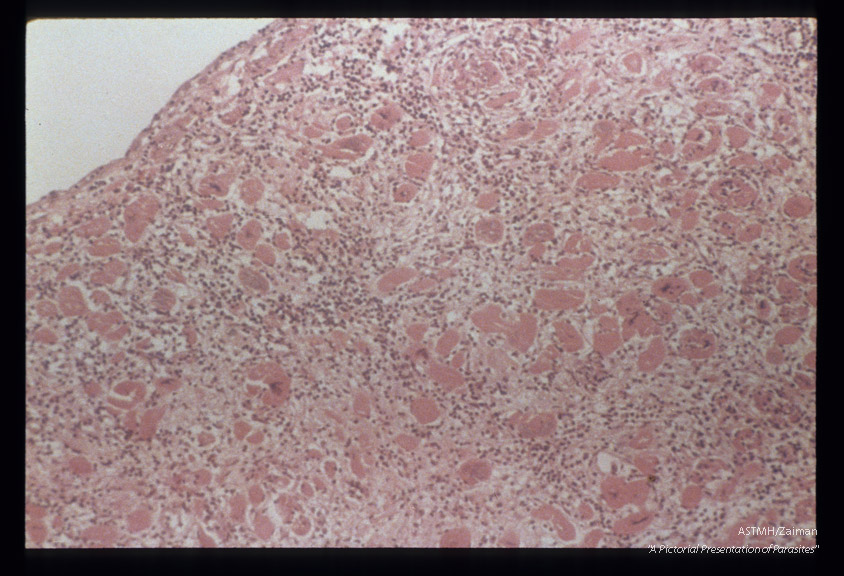

Hematoxylin-eosin stained section of myocardium showing inflammation, fibrosis and masses of leishmania forms.

Trypanosoma cruzi

Description: Hematoxylin-eosin stained section of myocardium showing inflammation, fibrosis and masses of leishmania forms.